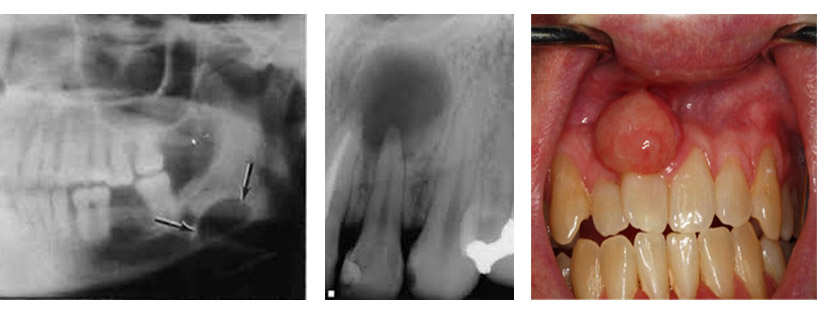

Υπάρχουν περιστατικά με επιπλέον του φυσιολογικού αριθμού δόντια στην άνω ή στην κάτω γνάθο. Τα υπεράριθμα δόντια μπορεί να είναι ασυμπτωματικά, μπορεί όμως να δημιουργούν προβλήματα όπως η παρεμπόδιση της ανατολής παρακείμενων δοντιών ή η πρόκληση επώδυνων συμπτωμάτων λόγω της πίεσης που ασκούν στα γειτονικά ανατομικά μόρια. Μετά από σωστή κλινική και απαραιτήτως ακτινογραφική μελέτη με τομογραφία κωνικής δέσμης (CBCT SCAN) προσδιορίζεται η θέση του υπεράριθμου δοντιού καθώς και ο ορθότερος τρόπος χειρουργικής προσπέλασης.

Στα οστά της άνω και κάτω γνάθου συχνά δημιουργούνται κοιλότητες που περιβάλλονται από μία μεμβράνη και περιέχουν υγρό, είναι απολύτως καλοήθεις και δημιουργούνται αυτόματα ή από νεκρά δόντια. Η χειρουργική αφαίρεση σε περιοχές με αυξημένο πάχος του εξωτερικού φλοιού του οστού μπορεί να απαιτήσει εκτεταμένη αφαίρεση αυτού και πιο σύνθετες μορφές αποκατάστασης.

Ακροριζεκτομή

Είναι μία τεχνική που χρησιμοποιείται κατά τη χειρουργική ενδοδοντολογία, κατά την οποία, εκτός από την αφαίρεση των παθολογικών περιακροριζικών ιστών, αποκόπτεται και αφαιρείται τμήμα του άκρου της ρίζας του δοντιού περίπου δύο με τρία χιλιοστά το οποίο στη συνέχεια εμφράσσεται με ειδικά βιοσυμβατά υλικά. Συνήθως εκτελείται μετά από μία αποτυχημένη ενδοδοντική θεραπεία και εφόσον η φύση των προβλημάτων που προκάλεσαν τις επιπλοκές της αρχικής ενδοδοντικής θεραπείας δείχνουν ότι η επανάληψη της δε θα είναι επιτυχής.